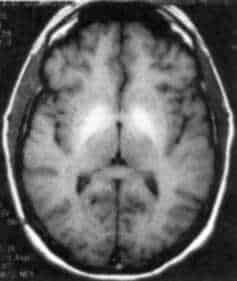

Imaging compound developed by Mass. General team produces comparable image enhancement to the standard of care with rapid clearance, less likelihood of toxicity. A team of Massachusetts General Hospital (MGH) researchers has developed a potential alternative to gadolinium-based contrast agents (GBCAs) for magnetic resonance imaging (MRI). In their report that has been published online in Radiology, […]